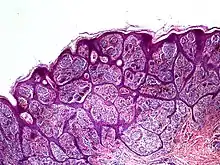

Nevoid melanoma is a cutaneous condition that may resemble a Spitz nevus or an acquired or congenital melanocytic nevus.[1]